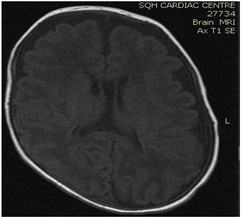

Brain MRI (images 1,2,3,4) at the age of 78 days; revealed that generalized relative simplified gyral pattern, generalized enlarged subarachnoid spaces as well as enlarged bilateral sylvian fissures, no diffusion restriction, no intracerebral hemorrhage, pituitary fossa appears normal in size, the posterior pituitary spot is not well defined.

Image 4

We were able to manage hypernatremia and polyuria with desmopressin and weaned the infant from a high fluid intake to a normal fluid intake per day [10-14]. The desmopressin response validated the diagnosis of central diabetes insipidus. Brain MRI data were also indicative of a central origin, particularly the posterior pituitary spot, which was not well delineated.  In comparison with previously reported cases, we controlled the case with a little dosage of oral desmopressin, and oral desmopressin is more practical than intranasal dDAVP treatment [15,16], and oral desmopressin administration and modification of dosage is easier than nasal application [17].